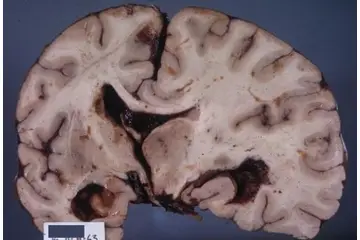

Beyin Dokusu Türleri ve Özellikleri Beyin, merkezi sinir sisteminin en önemli organı olup, karmaşık yapısıyla birçok işlevi yerine getirmektedir. Beyin dokusu, genel olarak iki ana türden oluşmaktadır: gri madde ve beyaz madde. Bu makalede, beyin dokusu türleri ve özellikleri detaylı bir şekilde incelenecektir. Gri Madde Gri madde, beyin yüzeyinde yer alan ve nöron hücre gövdelerinin (soma) yoğun olarak bulunduğu bölgedir. Gri maddenin başlıca özellikleri şunlardır:

Beyaz Madde Beyaz madde, beyin içerisindeki nöronların aksonlarının yoğun olarak bulunduğu bölgedir. Aksonlar, nöronlar arasındaki iletişimi sağlamak için elektriksel sinyaller ileten uzun uzantılardır. Beyaz maddenin özellikleri şunlardır:

Beyin Dokusunun Sağlık Üzerindeki Etkileri Beyin dokusunun sağlıklı bir şekilde işlev görmesi, genel sağlık üzerinde büyük etkiye sahiptir. Beyin dokusundaki hasar veya bozulmalar, birçok nörolojik hastalığın temelini oluşturur. Öne çıkan sağlık sorunları arasında: